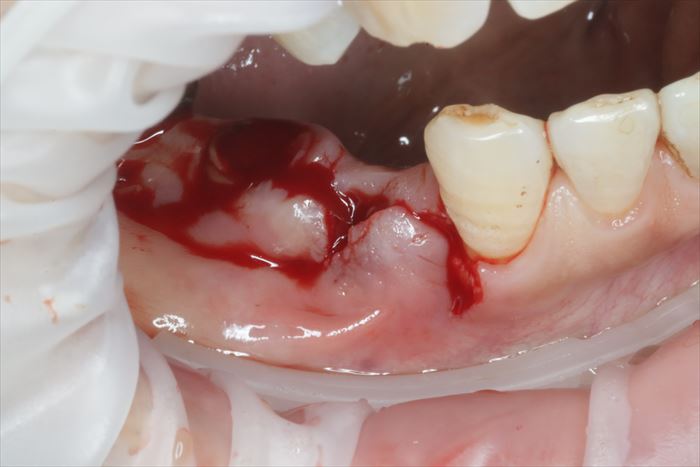

実際の右下小臼歯です。外観では排膿などはありません。

まずは連結部分を切断しました。

切断と同時にメタルコアまでが取れました。

連結してあったことで、インプラントと持ちつ持たれつのような関係を保っていたと考えられます。

周囲の歯肉を切開するとインプラントもかなりの動揺を見せます。